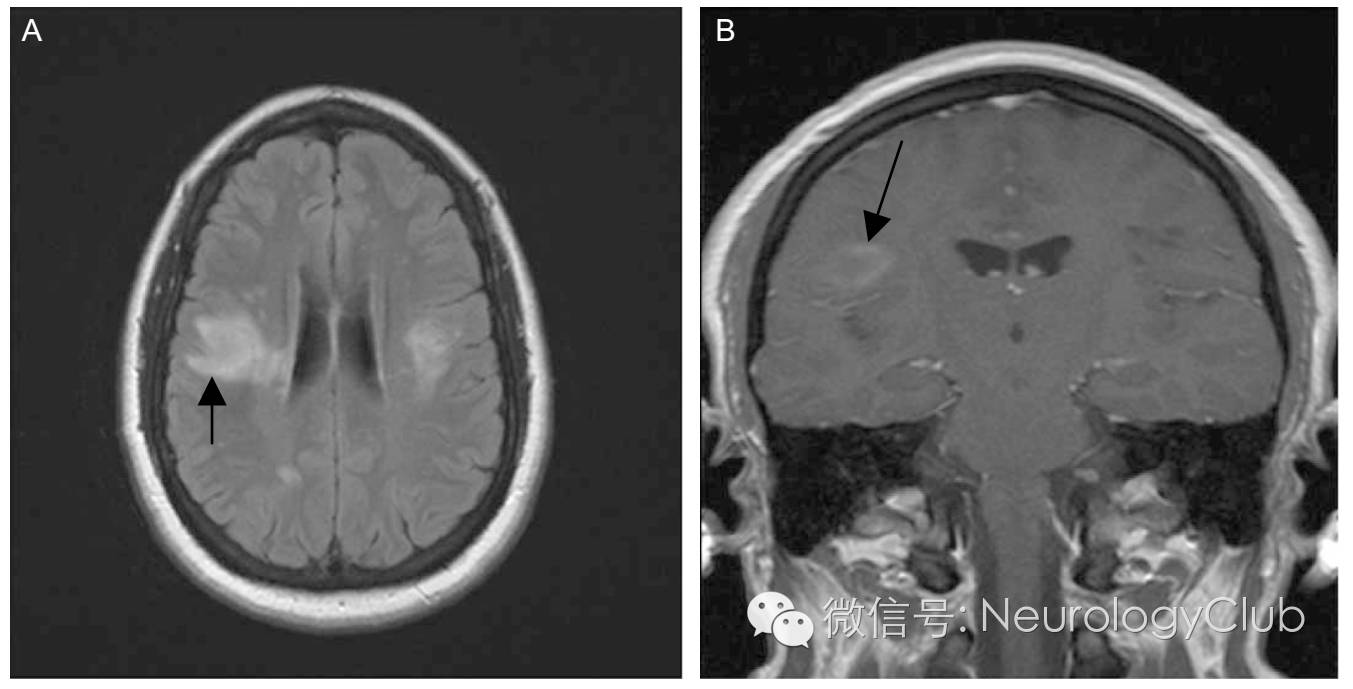

(图7:A:FLAIR可见右侧近皮层处外侧裂周病灶[箭],左侧亦可见;B:增强后右侧外侧裂周病灶强化)